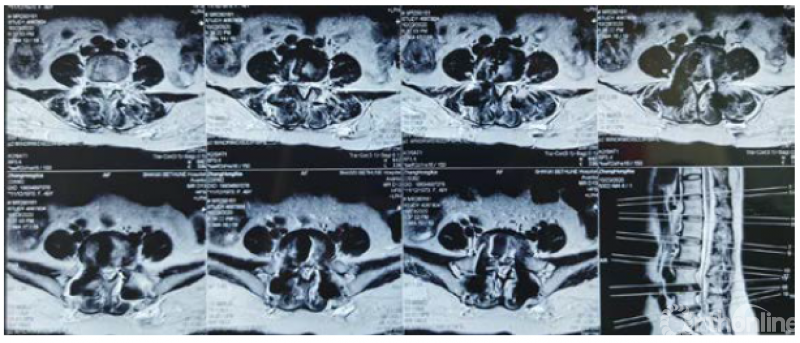

病例分享:(滑动查看)